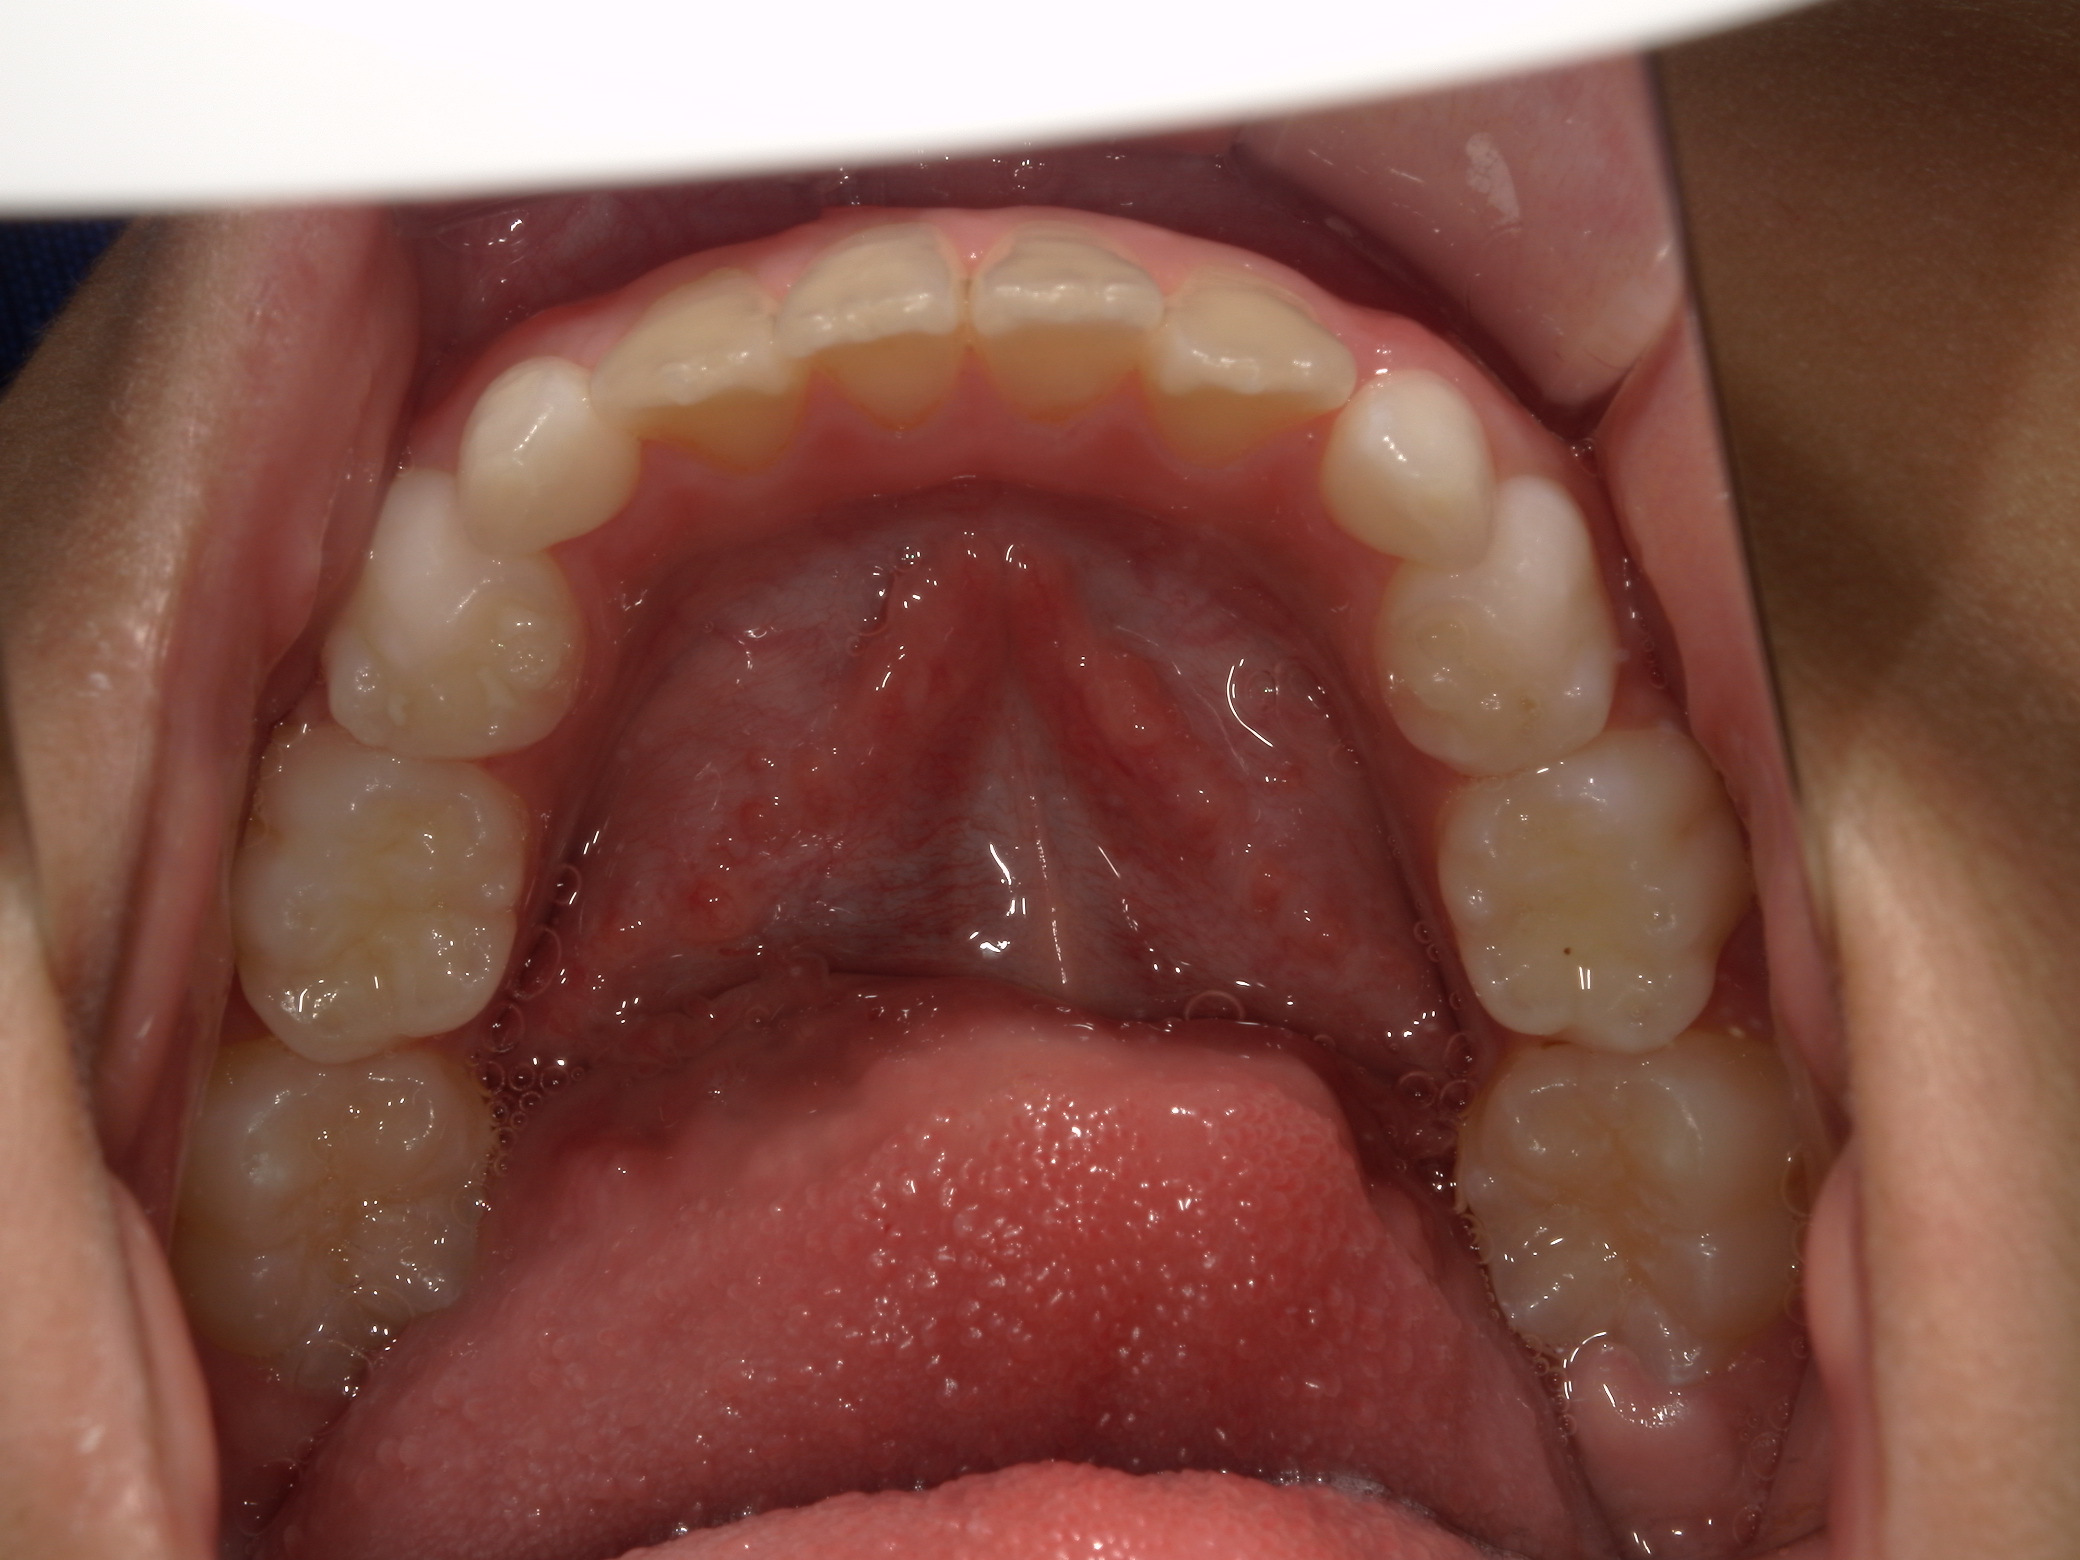

バイオネーターの症例

主訴 | 上の前歯が気になる |

---|---|

治療内容 | バイオネーター |

治療期間 | 1年 |

治療費用 | 330,000円(税込) |